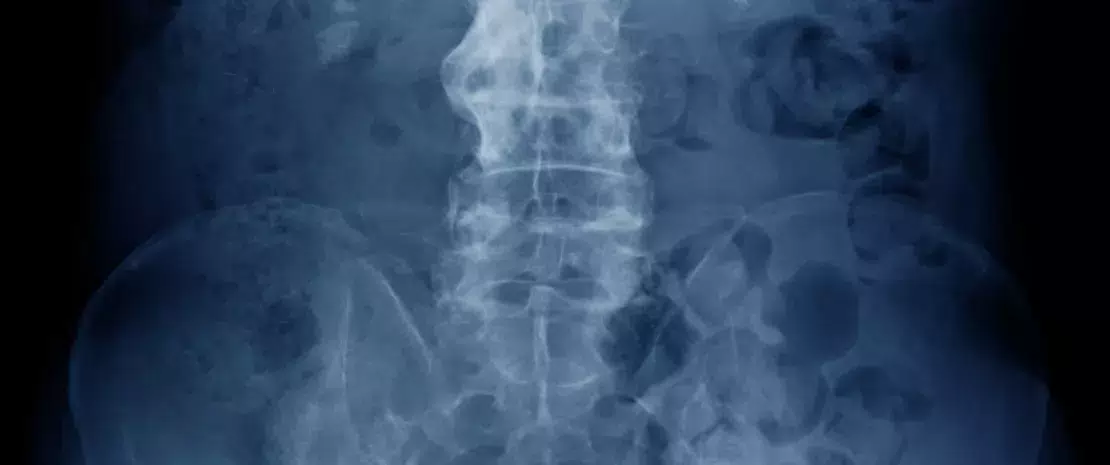

Photo : Ankylosing spondylitis: the role of fungal microbiota

Spondylarthrite ankylosante (SA) et dysbiose intestinale semblent liées : plus de 70 % des patients SA souffrent d’inflammation intestinale subclinique avec, pour 5 à 10 % d’entre eux, une forme sévère pouvant évoluer jusqu’à une maladie inflammatoire chronique de l’intestin (MICI). Si le microbiote intestinal bactérien de ces patients a déjà été analysé, aucune étude ne s’était encore penchée sur leur microbiote fongique (ou mycobiote). C’est désormais chose faite : une étude chinoise a caractérisé les microbiotes intestinaux bactériens et fongiques intestinaux de 22 patients SA et 16 témoins sains.